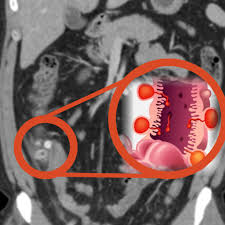

간은 인체에서 가장 큰 장기 중 하나로, 여러 가지 중요한 기능을 수행합니다. 간 질환은 매우 일반적인 문제로, 신속하고 정확한 진단이 필요합니다. 복부 CT를 통해 간의 경화, 종양, 지방간 등 다양한 문제를 확인할 수 있습니다. 특히 간암의 경우, CT 촬영은 초기 단계에서 종양의 크기와 위치를 평가하는 데 중요한 역할을 합니다. CT 이미지는 간 내 혈관과 주변 조직의 상태를 상세히 보여주기 때문에, 간암이 다른 장기로 전이되었는지 파악하는 데도 유용합니다.

간암은 조기 증상이 거의 없기 때문에 진단이 늦어지는 경우가 많습니다. 그러나 복부 CT를 통해 초기 증상을 발견할 수 있다면, 치료 옵션이 훨씬 다양해집니다. 간암의 원인으로는 간염 바이러스 감염, 알코올 남용, 비만 등이 있으며, 이들 요인을 관리함으로써 예방할 수 있습니다. CT 촬영을 통해 조기에 간암을 발견하면, 간 절제술이나 간 이식과 같은 치료를 통해 생존율을 높일 수 있습니다.